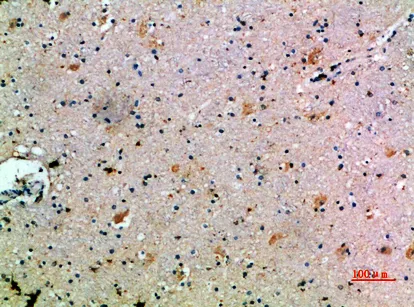

C3aR Rabbit Polyclonal Antibody($99/20μL)

Cat: APRab07746

Application:IHC-P,IF-P,IF-F,ICC/IF,ELISA

Reactivity:Human,Rat,Mouse

Gene Name:C3AR1